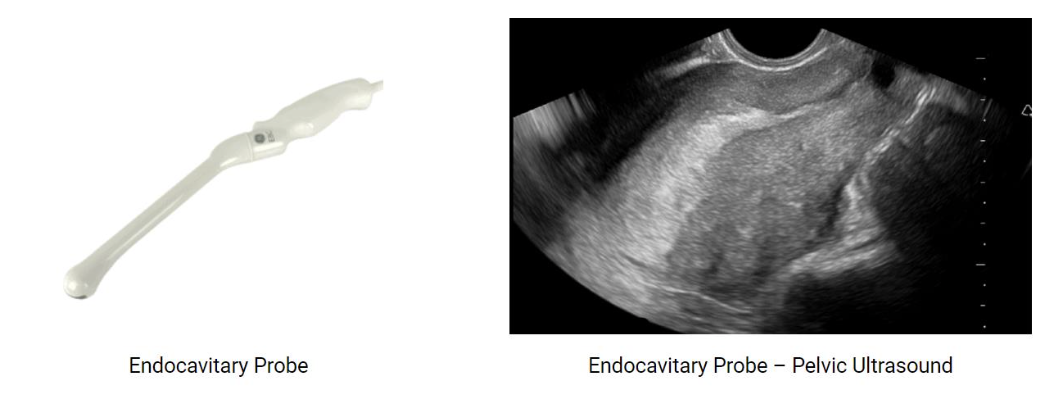

The Endocavitary probe

• Designed for internal imaging (e.g., transvaginal, transrectal).

• Higher frequency → better resolution, shallower penetration.

• Provides close proximity to organs for detailed assessment.

Transvaginal US

A transvaginal ultrasound is conducted with a 5-12 MHz, narrow

transvaginal probe

It is inserted into the vagina and then carefully moved by the

sonographer to obtain the images